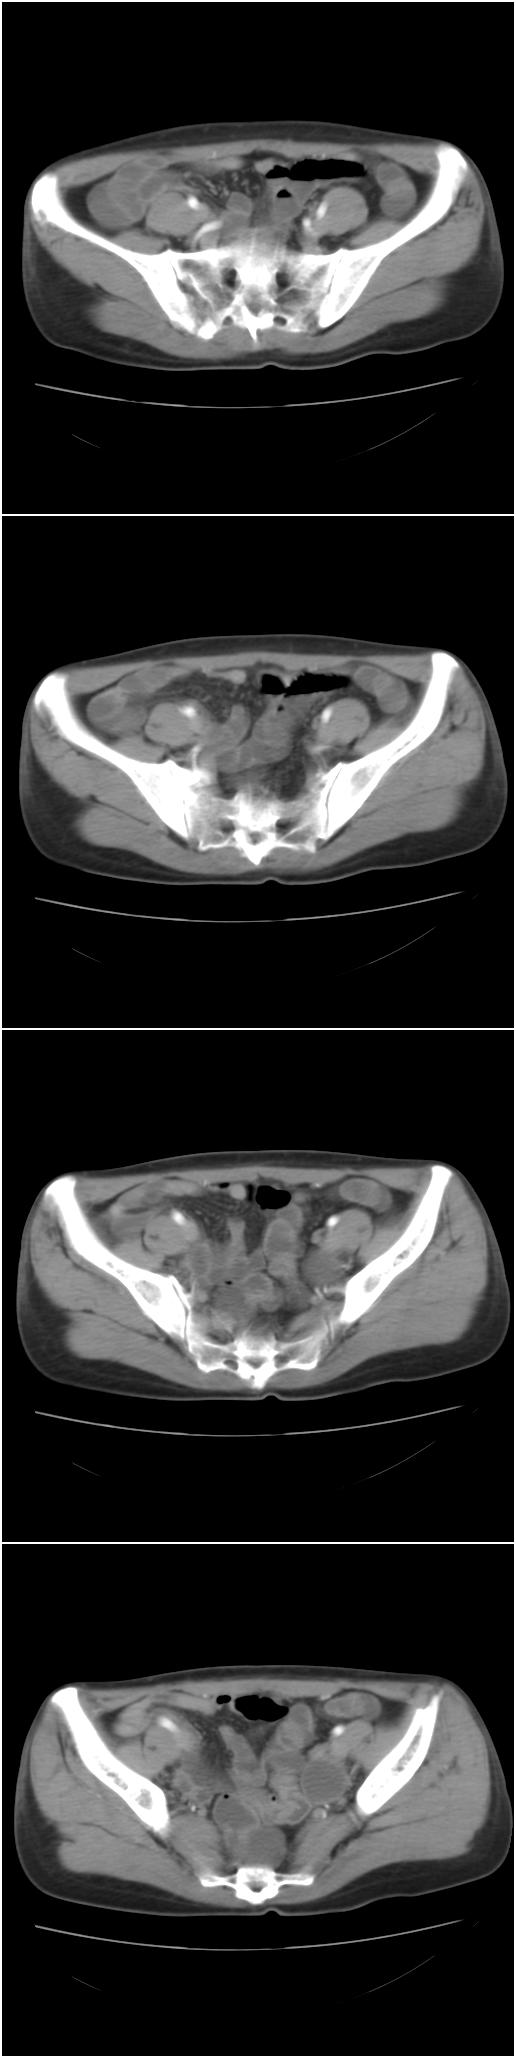

以下是今天的增强片,大家可以看看:

右侧髂骨后缘囊状膨胀性骨质改变,无明显骨间隔,周围无明显硬化及骨膜反应,周围软组织无异常,相邻骨组织密度增高,考虑:动脉瘤样骨囊肿可能,要注意与骨巨细胞瘤及转移瘤鉴别。

右侧髂骨膨胀性骨质破坏区 囊内密度尚均匀 骨巨细胞瘤可能性大 动脉瘤样骨囊肿不除外 建议mr观察囊内成分明确诊断 左侧附件区包裹性积液

右侧髂后上棘局限性囊状骨质破坏,大部分界清,似见轻度硬化边,内无分格及钙化,病灶上部局部显示模糊。考虑;骨巨细胞瘤可能大,不除外abc。另可见子宫肌瘤术后子宫缺如。

临床和影像学表现:女性患者46岁,有子宫肌瘤手术病史。影像所见可见残余宫颈部分,左右附件未见新生物;右髂骨翼后端囊状膨胀性骨破坏,囊性部分感觉有强化(楼主标上增强前后的ct值就很好了),未见明确的液—液平面,周边硬化不明显或轻度硬化。

分析:患者年龄46岁,没有明确外伤病史,病变呈膨胀性骨破坏,囊性部分未见明确的液—液平面,周边硬化不明显。综合分析该病例比较符合骨巨细胞瘤,不太符合动脉瘤样骨囊肿。